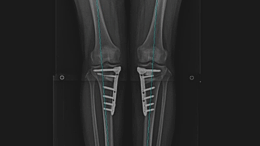

휜다리고정술

건강을 위한 사랑TV